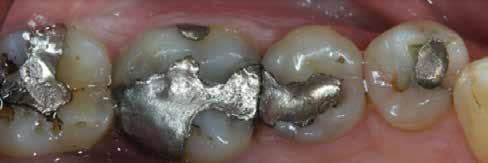

2. ábra: A páciens egy nem megfelelő I. osztályú ezüstamalgám töméssel és II. osztályú szuvasodással jelentkezett. A fog izolálása kofferdám alkalmazásával történt.

3. ábra: A preparálás, a bondozás és a kompozit felvitele után. (Megjegyzés: némi kompozit túlfolyás látható a mesiális doboz axiális falain).